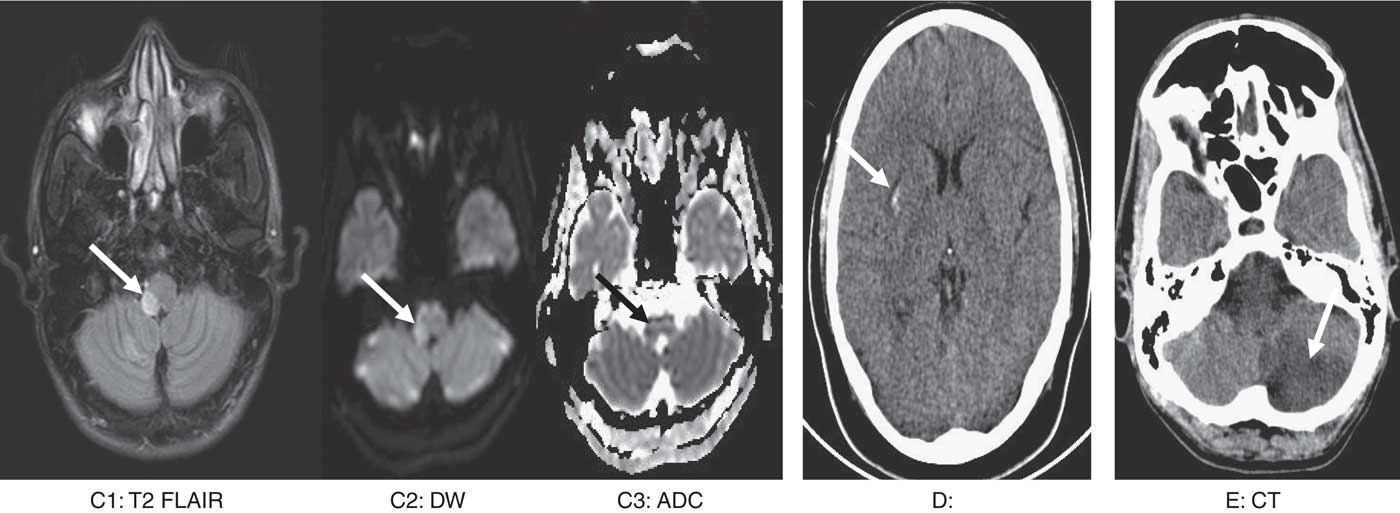

A total of 32 patients with scorpion sting and 35 patients with snake envenomation were included in the review, as shown in Table 1. Mean ages of patients with snake and scorpion envenomation were 43 and 33 years, respectively. There was a male preponderance among both the groups. Clinical features of depressed sensorium and hemiparesis were present in more than one-third of the patients with snake envenomation. Hemiparesis was present in more than half of the patients, and depressed sensorium was present in one-third of the patients with scorpion envenomation. CT brain was the most common neuroimaging performed for 54% and 81% of patients with snake and scorpion envenomation, respectively. Infarcts were the most common patterns of CVI and were seen in 88% and 53% with snake and scorpion envenomation, respectively. Among these, 68% of patients with snake envenomation and 47% of patients with scorpion sting had multiple infarcts. More than one infarct was defined as multiple infarcts. In all, 48.5% of patients with snake envenomation and 28.5% of patients with scorpion sting had infarcts bilaterally. Among the controls, 26 (74%) had infarcts, seven (20%) had hemorrhages and two (6%) had hemorrhagic infarcts. Among the controls, 13 (50%) infarcts were multiple and six (23%) were bilateral. Hemorrhages were more among patients with scorpion sting (41% vs. 6%). In all, 92% of patients with hemorrhage had single and unilateral involvement. Among the controls, all bleeds were single and unilateral. In the patients with scorpion sting, the most common sites of hemorrhage were capsuloganglionic region, similar to the controls, as shown in Table 2. The most common sites of infarcts following both the envenomations were parieto-occipital, cerebellar and capsuloganglionic and frontal region, respectively (Images 1 and 2). These were also similar to the topography of infarcts in age-matched controls (Table 2). Mortality in patients with cerebrovascular accidents following snake envenomation was 8%, as compared with 28% in patients with scorpion envenomation and 5.7% in age-matched controls.

Image 2 Image series (C) a 45-year-old lady with scorpion sting. T2 flair image shows hyperintensity and expansion. Corresponding area shows diffusion restriction suggestive of acute right lateral medullary infarct. (D) A 29-year-old man with scorpion sting. Non-contrast CT brain show acute hemorrhage in the right putamen. (E) A 47-year-old man with scorpion sting. Non-contrast CT brain shows acute infarct in the left posterior inferior cerebellar artery territory.

Both CT and MRI have been used for confirmation of CVI among these patients. CT brain was performed for 75% of patients with scorpion sting and 53% of patients with snake envenomation in our review. Although CT is adequate to establish the diagnosis, an MRI with diffusion restriction is ideal in differentiating dilated venules and artifacts, which could be mistaken for infarcts.Reference Mishra, Arvind and Muliyil 30 In both, infarcts and hemorrhages can be seen, with the former being common. Infarcts tend to be bilateral and multiple. Infarcts following both the envenomations were predominant in parieto-occipital, cerebellar and capsuloganglionic regions, respectively (Images 1 and 2). Involvement of bilateral anterior cerebral artery, middle cerebral artery and the posterior cerebral artery is common, with the involvement of bilateral posterior cerebral artery reported to be most common.Reference Kumar, Babu and Agrawal 31 – Reference Thacker, Lal and Misra 39 The uncommon neurological involvements that have been reported are the presence of thalamic infarct, lateral medullary syndrome and brainstem infarcts.Reference Ittyachen and Jose 24 , Reference Kumar, Babu and Agrawal 31 , Reference Fernández-Bouzas, Morales-Reséndiz, Llamas-Ibarra, Martínez-López and Ballesteros-Maresma 35 , Reference Thomas, George, Mishra, Mannam and Ramya 40 Hemorrhages tend to be unilateral and single. Common sites of hemorrhage are capsuloganglionic region, cortical and cerebellar, respectively (Table 2) (Images 1 and 2). Patients can also present with coexistent infarcts and hemorrhages, which was 6% in this review.Reference Namal Rathnayaka, Kularatne, Kumarasinghe, Ranaweera and Nishanthi Ranathunga 11 , Reference Boviatsis, Kouyialis, Papatheodorou, Gavra, Korfias and Sakas 32